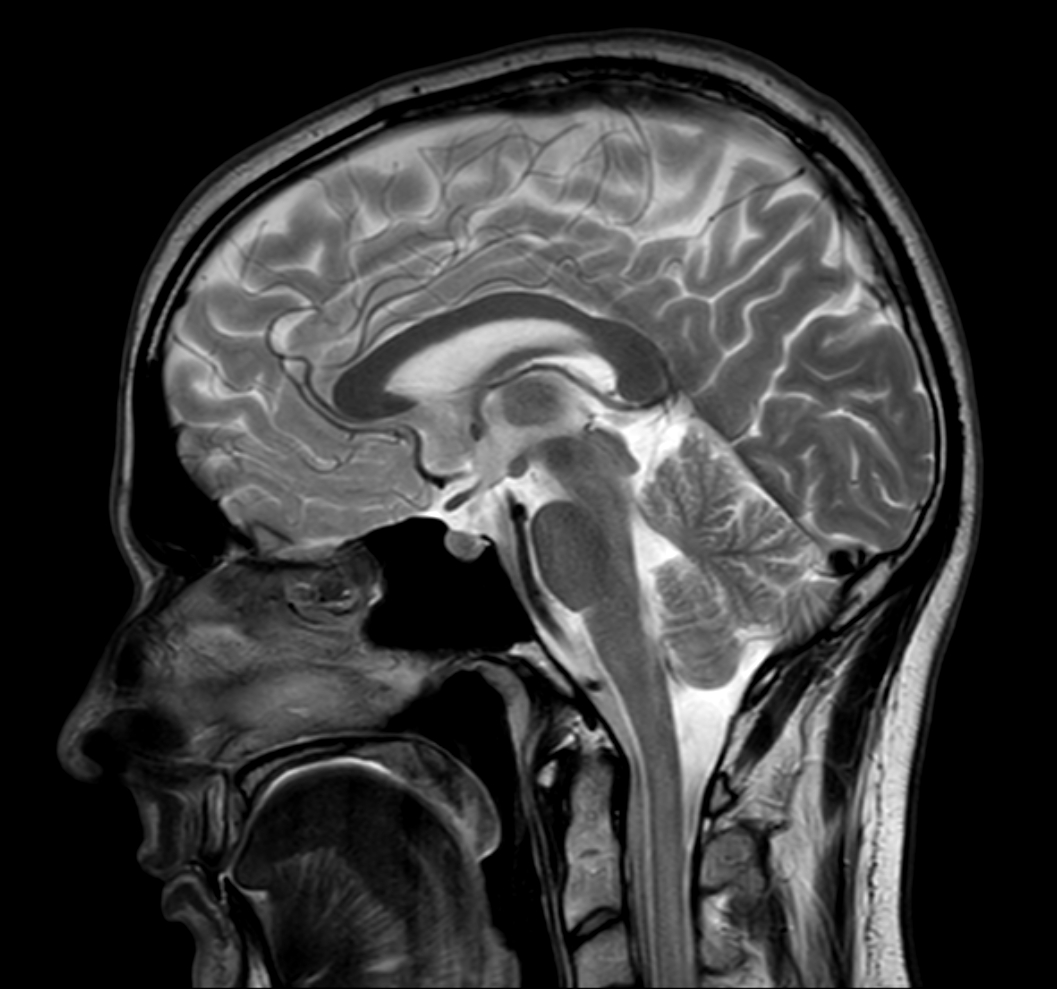

Sagittal T2w TSE with ComforTone